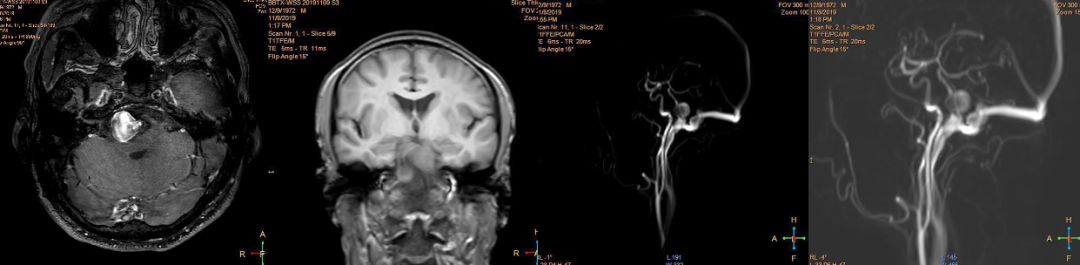

图3 术前椎动脉造影

图4 术前MR